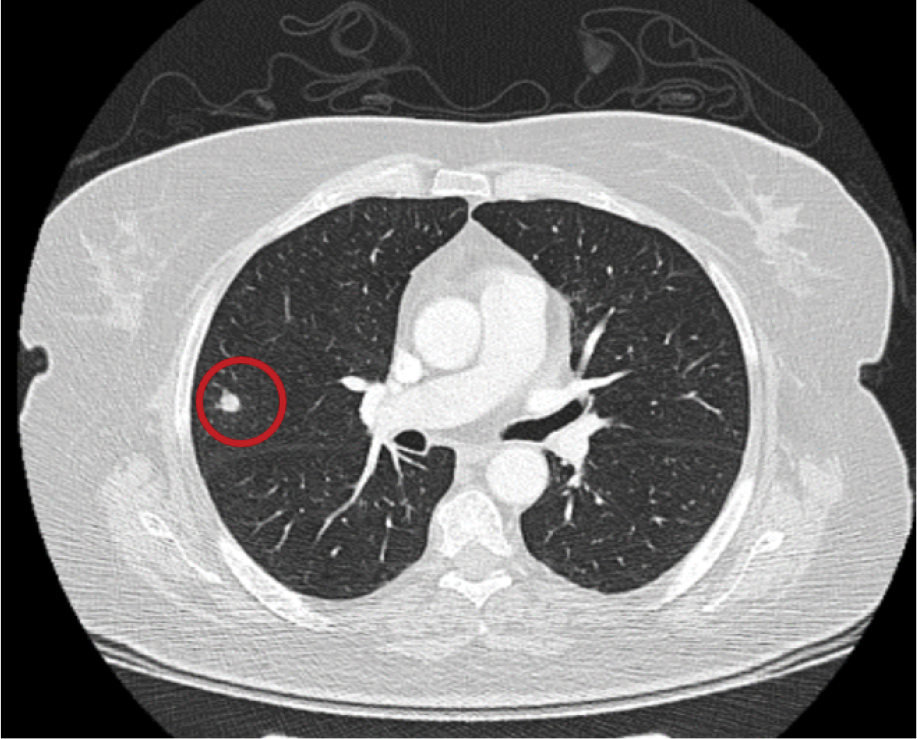

Repeat blood cultures were obtained, and thoracic computed tomography (CT) revealed a 9 mm, round-shaped nodular opacity in the posterior segment of the right upper lobe, suggestive of an infectious process—most likely fungal pneumonia (Figure 1). Physical examination also revealed toenail changes consistent with onychomycosis.